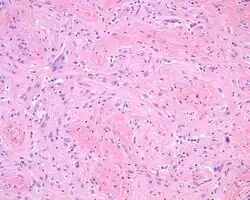

The overlying skin or squamous mucosa is intact and uninvolved by the process. There is normal glial tissue set within a fibrous connective tissue stroma. There is such blending, that the underlying process may be difficult to detect without special studies. In a few cases, large gemistocytes, neurons, choroid plexus, ependyma, and retinal pigmented cells may be seen.[2][3]

Histochemistry

A trichrome stain will highlight the dual components well, with the glial tissue staining red, while the background fibrosis stains a bright blue.[2]

Immunohistochemistry

The glial tissue is highlighted with S100 protein and with glial fibrillary acidic protein, although the latter is much more sensitive for glial tissue.[2]